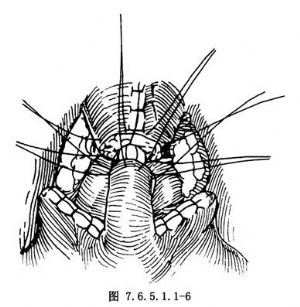

6. 3-0可吸收線將膀胱肌管與後尿道斷端縫6針後按順序打結,完成吻合。男性患者可在膀胱前壁近管處用2-0可吸收線縫2針,從低位腹直肌鞘穿出,打結後可起到上提膀胱、減輕吻合口張力的作用。女性則將腸線縫於陰道前壁進行懸吊(圖7.6.5.1.1-6)。